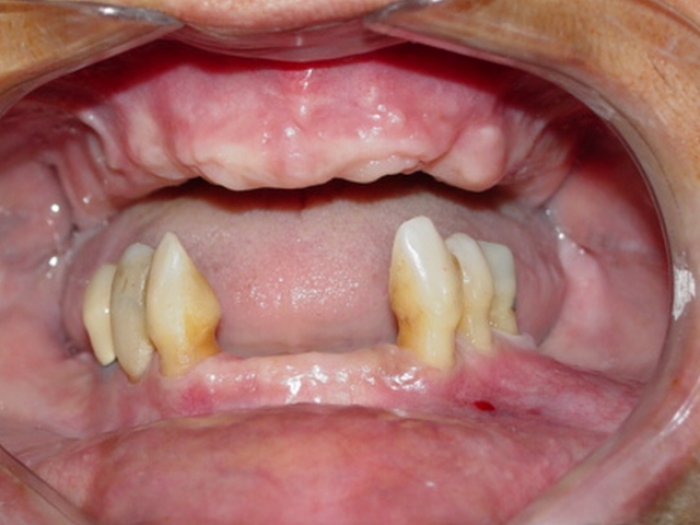

Imagem inicial